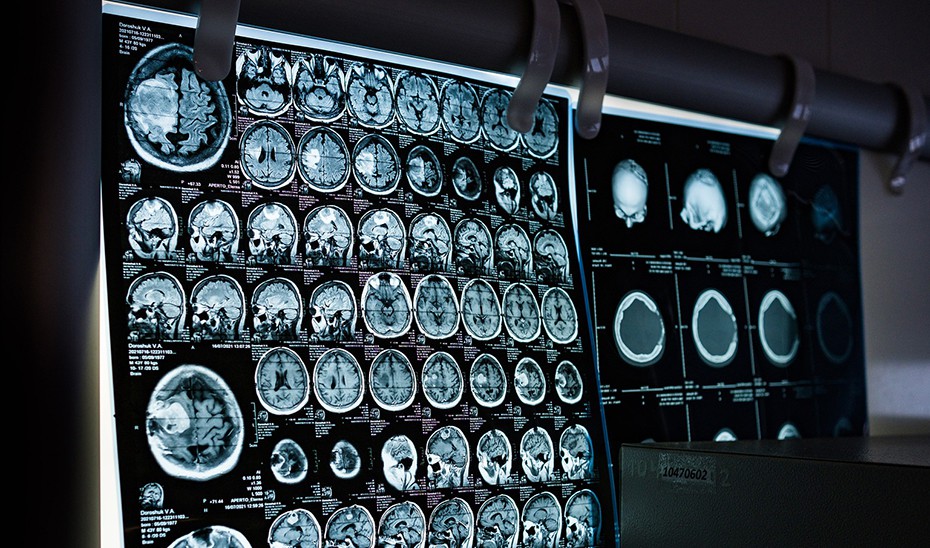

La Consejería de Sanidad, Presidencia y Emergencias ha dado un paso significativo al incorporar la terapia de campos eléctricos alternos, conocida como ‘TTFields’, para el tratamiento del glioblastoma, uno de los tumores cerebrales más agresivos. Esta innovadora tecnología utiliza dispositivos externos que ayudan a frenar o ralentizar el crecimiento tumoral, mejorando así la supervivencia y la calidad de vida de los pacientes afectados.

Nuevas oportunidades en el tratamiento del glioblastoma

Hasta ahora, el tratamiento estándar del glioblastoma incluía cirugía, radioterapia y quimioterapia. Con la introducción de esta terapia, Andalucía realiza un «salto cualitativo» en la atención a estos pacientes. «Era fundamental ofrecer una respuesta innovadora y útil ante una enfermedad con un pronóstico complicado. ‘TTFields’ nos permite hacerlo con rigor, seguridad y equidad territorial», añadió Sanz.

A pesar de ser un cáncer poco frecuente —con una incidencia estimada entre tres y cinco casos por cada 100.000 habitantes— el glioblastoma es altamente agresivo, presentando una supervivencia media de solo 14 a 16 meses incluso con los tratamientos más avanzados disponibles actualmente.